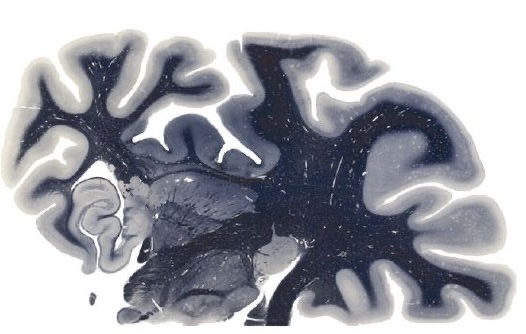

Если бы ноотропы реально работали, как заявлено в описании, то мир бы наверное выглядел по другому. Но, к великому сожалению, большинство препаратов, установленных как питающий и восстанавливающий нервную систему - это пустышка. Пустышка именно для нервной системы. Начнем с того, что нервная система, как известно, не восстанавливается, а именно речь про нейроны, но что восстанавливается точно - это нейроглия и отростки нейронов. Это происходит тогда, когда возникло какое либо травматическое происшествие, либо же смерть клеток в результате нарушения кровообращения - инсульт. Тогда, как и корочка на коже с целью защиты раны, клетки вокруг нейронов начинают обустраивать место происшествия с целью восстановления структуры. Даже если это место регулярно орошать мексидолом и запивать все это дело глицином - процесс быстрее не пойдет, а пойдет ровно с такой скоростью, с которой ему позволит организм. Если же вы все таки стали тем человеком, на которого якобы подействовал тот или иной препар

Если бы ноотропы реально работали, как заявлено в описании, то мир бы наверное выглядел по другому. Но, к великому сожалению, большинство препаратов, установленных как питающий и восстанавливающий нервную систему - это пустышка. Пустышка именно для нервной системы. Начнем с того, что нервная система, как известно, не восстанавливается, а именно речь про нейроны, но что восстанавливается точно - это нейроглия и отростки нейронов. Это происходит тогда, когда возникло какое либо травматическое происшествие, либо же смерть клеток в результате нарушения кровообращения - инсульт. Тогда, как и корочка на коже с целью защиты раны, клетки вокруг нейронов начинают обустраивать место происшествия с целью восстановления структуры. Даже если это место регулярно орошать мексидолом и запивать все это дело глицином - процесс быстрее не пойдет, а пойдет ровно с такой скоростью, с которой ему позволит организм.